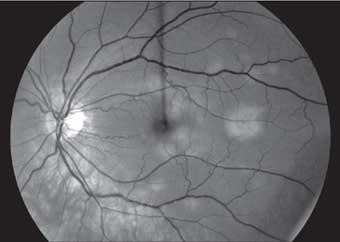

In 1968, Gass first described this self-limited inflammatory condition, acute posterior multifocal placoid pigment epitheliopathy (APMPPE), in which multiple white-yellow placoid lesions develop at the level of the retinal pigment epithelium and cause a rapid reduction of central vision in otherwise healthy young adults. The yellow-white retinal lesions fade to patches of RPE atrophy and hypertrophy, though all phases may be observed simultaneously. The visual changes typically recover within three weeks, though recovery may be limited with foveal involvement. Characteristic early hypofluorescence and late hyperfluorescence on fluorescein angiography (Figures 7 and 8) may be related to choroidal ischemia and a resultant delay in filling. Given an association with HLA-B7 and HLA-DR2, an immune-mediated mechanism and genetic susceptibility have been proposed. RP

Figure 8. At presentation, late-phase fluorescein angiogram showing delayed hyperfluorescence of RPE lesions.